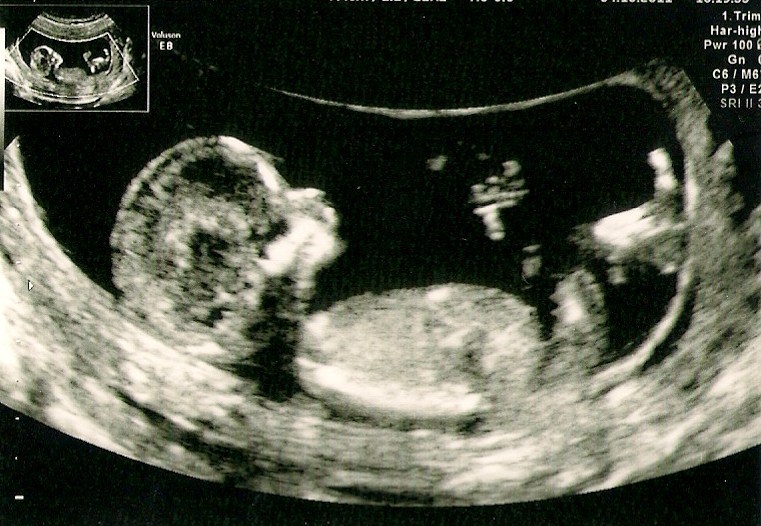

Jeg synes lige jeg ville komme med en update.... jeg var i sidste uge tirsdag d. 4 okt til nakkefold......... og den har jeg jo ikke særlig gode erfaringer med.. så hoooold da op tror aldrig jeg har været så nervøs før....... mit hjerte bankede løs og tårene begyndte at trille allerede inden den søde søde sygeplejeske var begyndt at scanne...... men HELDIGVIS var der en deeeeejlig spire derinde som var i fuuuuld vigør!!!!... den var dælme i hopla... det endte med hun scannede i næsten 3 kvarter fordi den ikke ville ligge stille

Men fik et risiko tal der hedder 1: 9967 så er godt tilfreds :-)

Nå men til sidst synes jeg da lige i skal se den lille spire i maven :-)